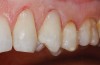

Figure  9  A Class V non-carious cervical lesion.

Figure 9

Figure  10  The Class V lesion restored with self-adhesive resin-based composite.

Figure 10

If the centric relation and centric occlusion in the presence of tooth surface loss is the same, or the dento-alveolar compensation has occurred, the teeth should be restored.54 The restorations can include Class V or palatal restorations, or reproduction of the cusps (Figure 9). Also, restorations can include covering the affected tooth surfaces with resin-based composites, using a sandwich technique, or placement of metallic, porcelain-fused-to-metal, or ceramic crowns (Figure 10, Figure 11, Figure 12, Figure 13, Figure 14, Figure 15 and Figure 16).